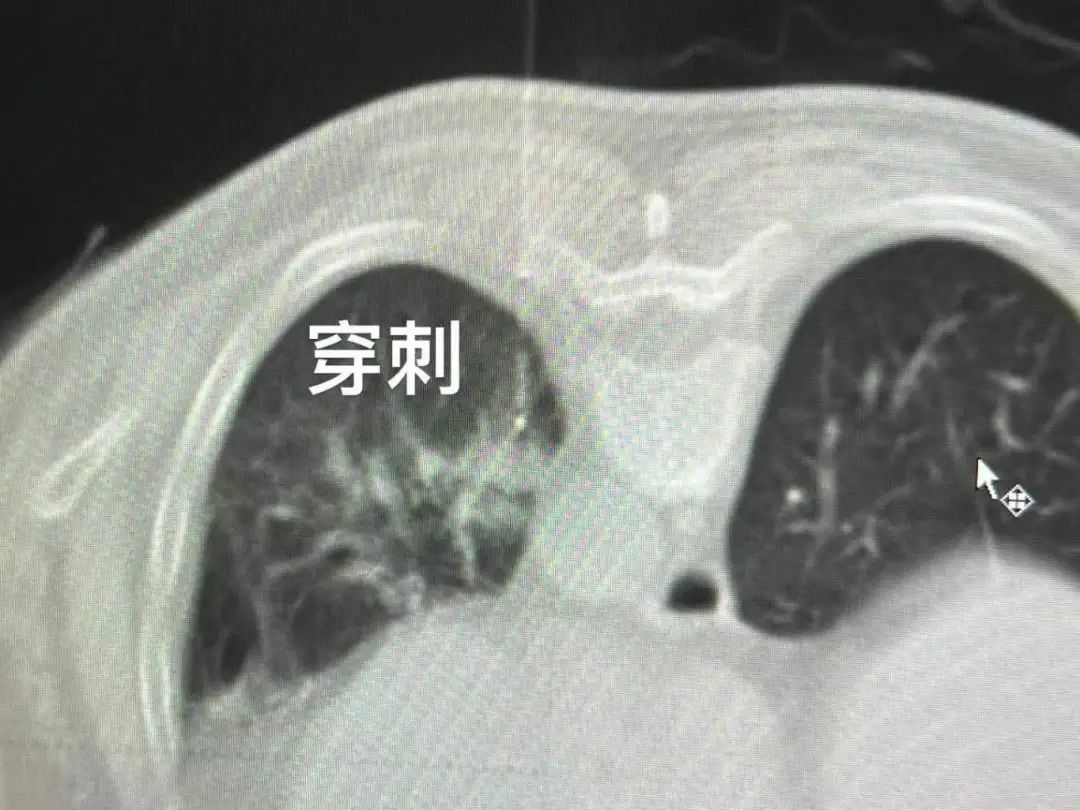

紧靠在主动脉的肺结节

有一位来自福建患者,五年前曾因右肺结节接受了手术切除术。后来左肺又长新的结节,二次手术创伤大,于是患者选择了射波刀治疗。可结节反而长大,并紧靠主动脉,如果消融,容易导致消融不完全,并损伤喉返神经。因此,我在消融前进行人工气胸术,将结节跟主动脉隔开,顺利完成结节的冷冻消融。